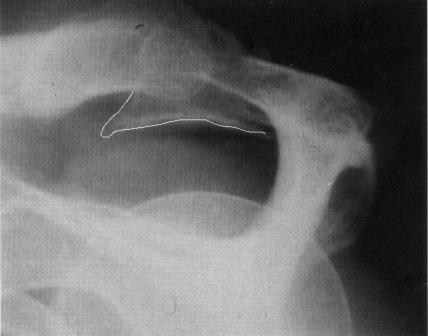

Supraspinatussenen

kommer i klemme under en prominerende acromion. Dette kan medføre en

hævet og øm slimsæk, som yderligere forværrer pladsforholdene, figur 1.

Figur 1.